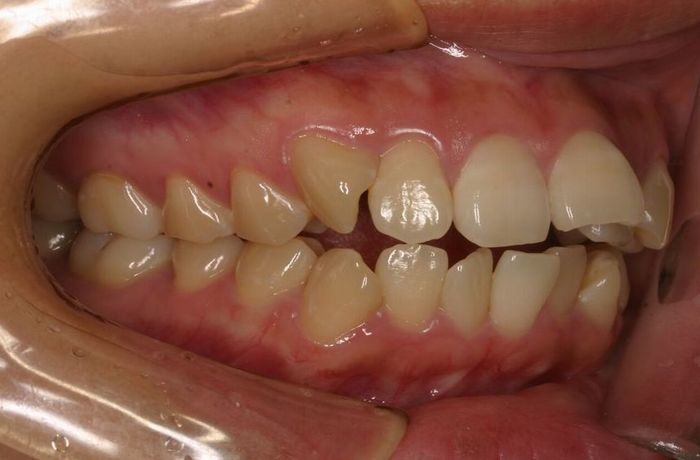

Case 2

主訴:  噛みにくい

診断:  アングルⅠ級 叢生

治療方針:

患者さんは26歳の女性で、上下顎の叢生による審美障害と咬合異常を訴えた。セファロ分析の結果、U-1 to FHおよびL-1 to Mandibularは1S.D.を超えて小さい値であった。その為、上下顎の叢生量は大きいが、上下前歯部の舌側傾斜による口元の落ち込みを防止する目的で、非抜歯で治療を行うことにした。

治療期間: 1年4カ月

費用:

診断費30000円、装置費用600000円、保定装置費用50000円、月1回の調整費4000円  (全て税別)

【 治療前 】

【 治療後 】